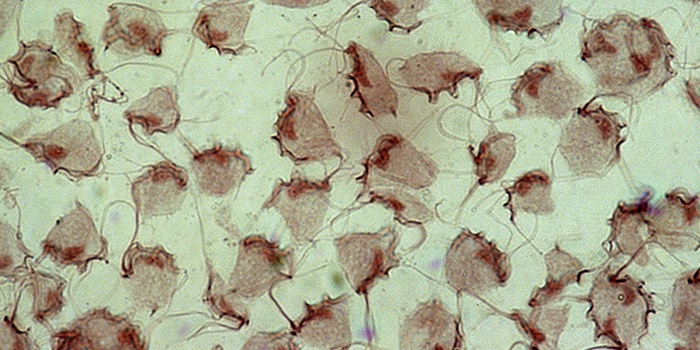

Трихомоніаз – хвороба, викликана збудником, який пристосований до існування всередині організму, за його межами він гине. Згубною для трихомонади є і підвищена температура, за винятком людського спека під час хвороби. Захворювання може протікати безсимптомно (особливо у чоловіків). У жінок з’являється подразнення піхви, рясні виділення жовтого або зеленуватого кольору.

Всі перераховані вище ознаки є для трихомоніазу основними, але вони можуть сигналізувати і про наявність інших інфекцій або захворювань, що передаються статевим шляхом. Іноді симптоматика захворювання дуже слабка, невеликий дискомфорт в області живота, слабкі виділення, на які жінка навіть не звертає уваги, відсуває думки про відвідини гінеколога на другий план, посилюючи ситуацію. Підтвердити наявність захворювання зможе тільки фахівець за допомогою лабораторного аналізу (взяття мазка) і діагностики.